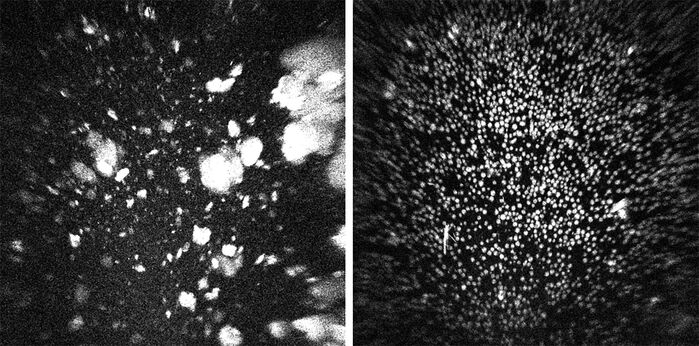

과거에 비해 발사 비용이 줄었다지만 여전히 비싼 비용과 각종 위험을 감수하고 우주로 가야 하는 이유는 바로 '미세중력'에 있습니다. 바이오 의약품의 주성분인 단백질을 지상에서 만들 때는 중력으로 인한 침전, 대류 현상을 피할 수 없습니다. 분자들이 바닥에 가라앉고 서로 엉겨 붙기도 해서, 결정이 울퉁불퉁하고 크기도 들쑥날쑥합니다. 불순물이 끼어들기도 쉽습니다. 반면 우주 공간의 미세중력 상태에서 침전, 대류 현상 없이 천천히 자라난 결정은 크기가 균일하며 순도가 높습니다. 순도 높은 단백질 결정은 매우 복잡한 단백질의 구조에 대한 이해를 돕고, 효과적인 신약을 개발하는 데 결정적인 도움을 줍니다. 고농도면서 점도는 낮은 단백질로의 변화, 즉 키트루다 제형 변화도 바로 여기서 시작된 것입니다.

지상 제조 단백질 결정(좌)-우주 제조 단백질 결정(우) (출처=다국적 제약사 머크)

▲ 지상 제조 단백질 결정(좌) - 우주 제조 단백질 결정(우) (출처=다국적 제약사 머크)